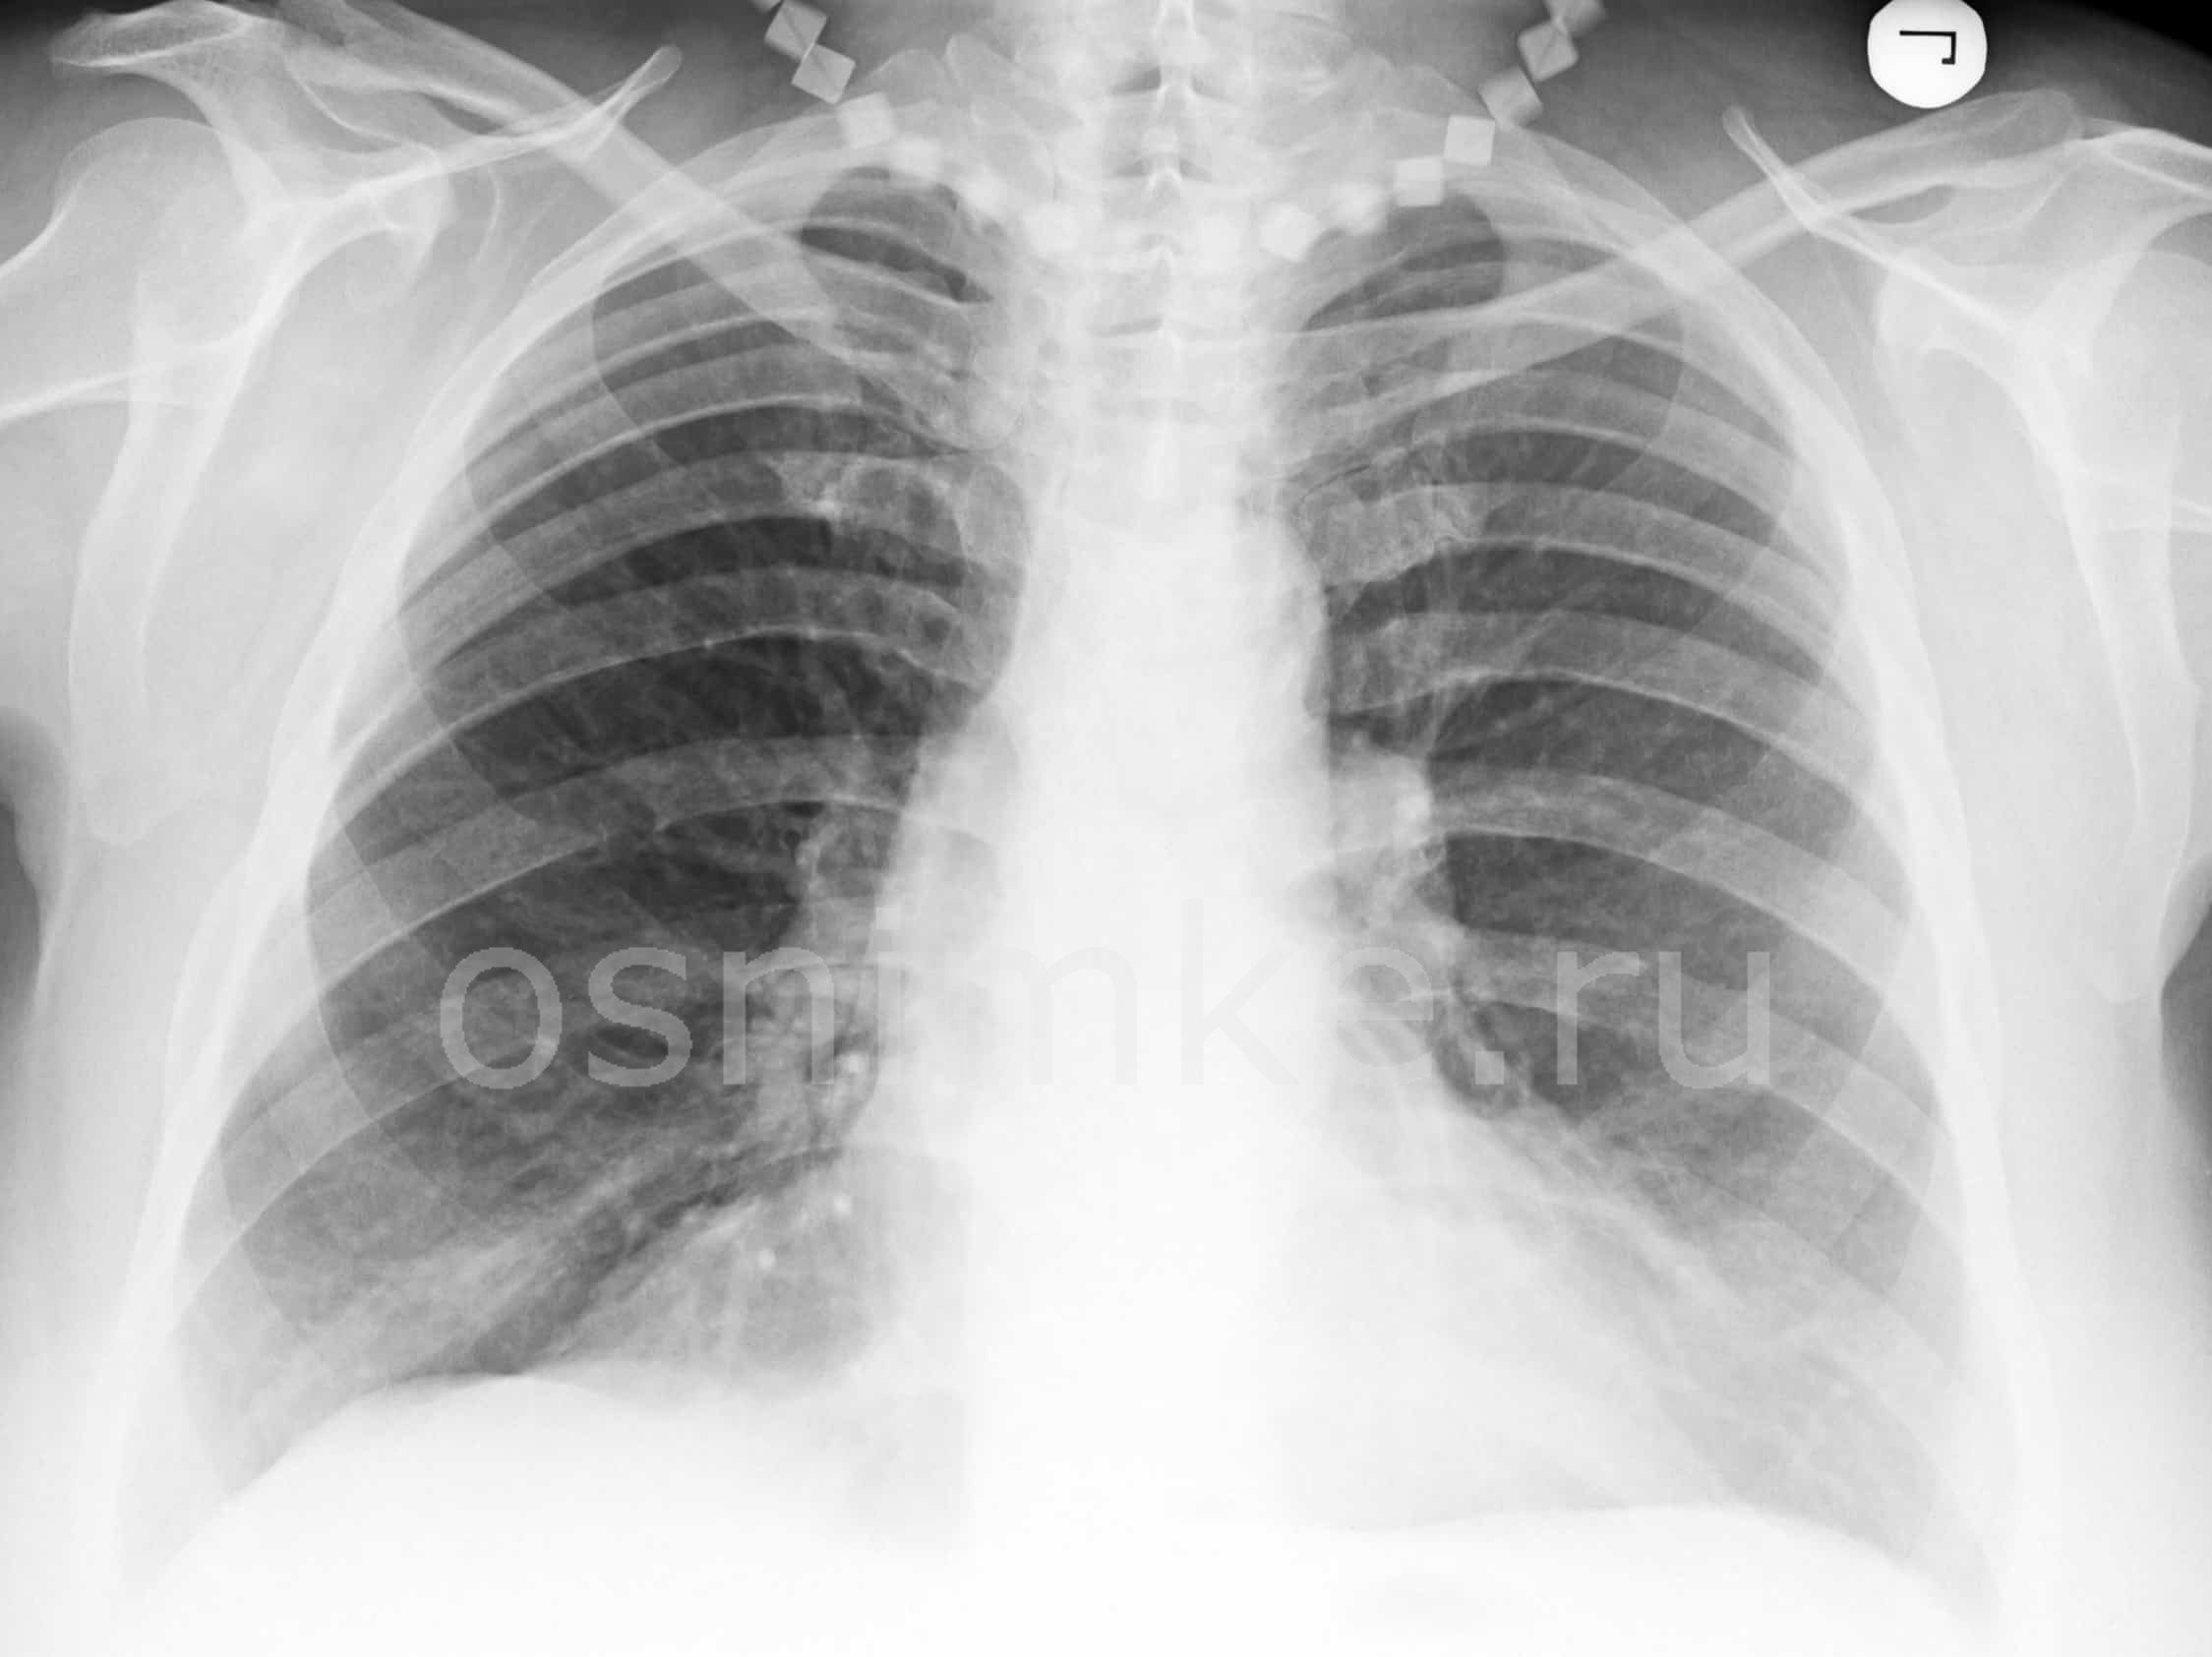

Как выглядит недуг на снимке

После проведения рентгенографии снимки должен изучить специалист, и на основе полученных данных и результатов других исследований сделать соответствующие выводы и поставить диагноз. В норме легкие и бронхи человека выглядят следующим образом:

- легочные доли имеют одинаковый, равномерный черный оттенок;

- в районе сердца наблюдается белый просвет;

- ребра и ключицы серые, с привычными очертаниями;

- купола диафрагмы белого цвета;

- позвоночный столб расположен в центре.

Признаки пневмонии на рентгеновском снимке во многом зависят от формы заболевания и его стадии, а также от локализации патологического процесса. Если исследование показало признаки пневмонии, необходимо как можно скорее приступить к лечению – запущенный патологический процесс опасен не только для здоровья, но и для жизни человека.

Основные признаки, описание

Первый признак пневмонии на рентгеновском снимке – появление очагов затемнения с неровными контурами в разных частях легкого, которые могут иметь разный размер, от 3-4-х до 12 мм.

Тени различают по внешнему виду (круглые, овальные кольцевидные) и интенсивности окраски – чем темнее пятно, тем сильнее выражен патологический процесс.

При поражении лимфатических узлов и нарушении кровоснабжения органа могут наблюдаться изменения корней легких, а если болезнь затронула плевру – нарушение в рисунке куполов диафрагмы. В остальном проявления пневмонии зависят от стадии, формы и клинических особенностей заболевания:

- Очаговая форма. На рентгене отображаются небольшие (1-1,5 см) тени со слабой или умеренной интенсивностью окраски, неоднородной структурой и нечеткими границами. Очаги поражения могут быть единичными или множественными, а в некоторых случаях они сливаются в одно большое пятно. Корни легких расширены, причем нарушения нормального рисунка органа могут сохраняться в течение нескольких дней после выздоровления.

- Крупозная пневмония. Наблюдаются изменения нормального легочного рисунка, жидкость в полости плевры, признаки инфильтрации одной из долей легкого, расширение корней. По мере развития воспалительного процесса выраженность изменений и интенсивность окраски затемнений усиливается.

- Интерстициальная форма. На снимке заметно уплотнение корней легких и другие изменения, которые формируют выраженный рисунок, напоминающий ветви дерева.

- Абсцедирующая пневмония. Проявляется обширным затемнением пораженной области, признаками утолщения плевры и наличием полостей разного размера, наполненных жидкостью.

- Аспирационная форма. Рентген характеризуется треугольными пятнами с однородной структурой, светлыми очагами и приподнятой диафрагмой.